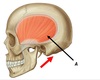

Name muscle A

A - Temporalis

Name muscle A

A - Masseter

Name muscle A

A - Lateral pterygoid

Name muscle A

A - Medial pterygoid